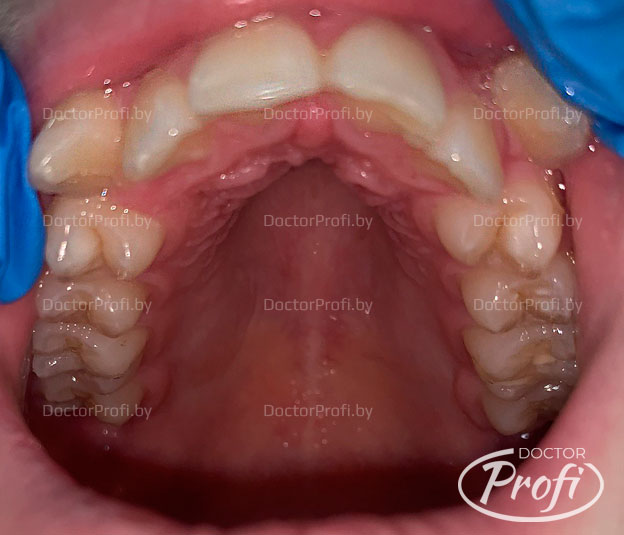

Пациент обратился в клинику с жалобами на эстетический дефект зубного ряда. На консультации у ортодонта были выявлены следующие проблемы с прикусом: сужение и укорочение зубных дуг, вестибулярное положение зубов 13, 23, 43, скученность резцов верхнего и нижнего зубного ряда.

- Проведена коррекция прикуса. Улучшена форма зубных рядов и положение зубов.

- Исправлено вестибуляное положение клыков.

В результате ортодонтического лечения (срок 24 месяца) мы получили хорошее функциональное и эстетическое состояние зубов. Пациент обрел красивую улыбку и правильный прикус.